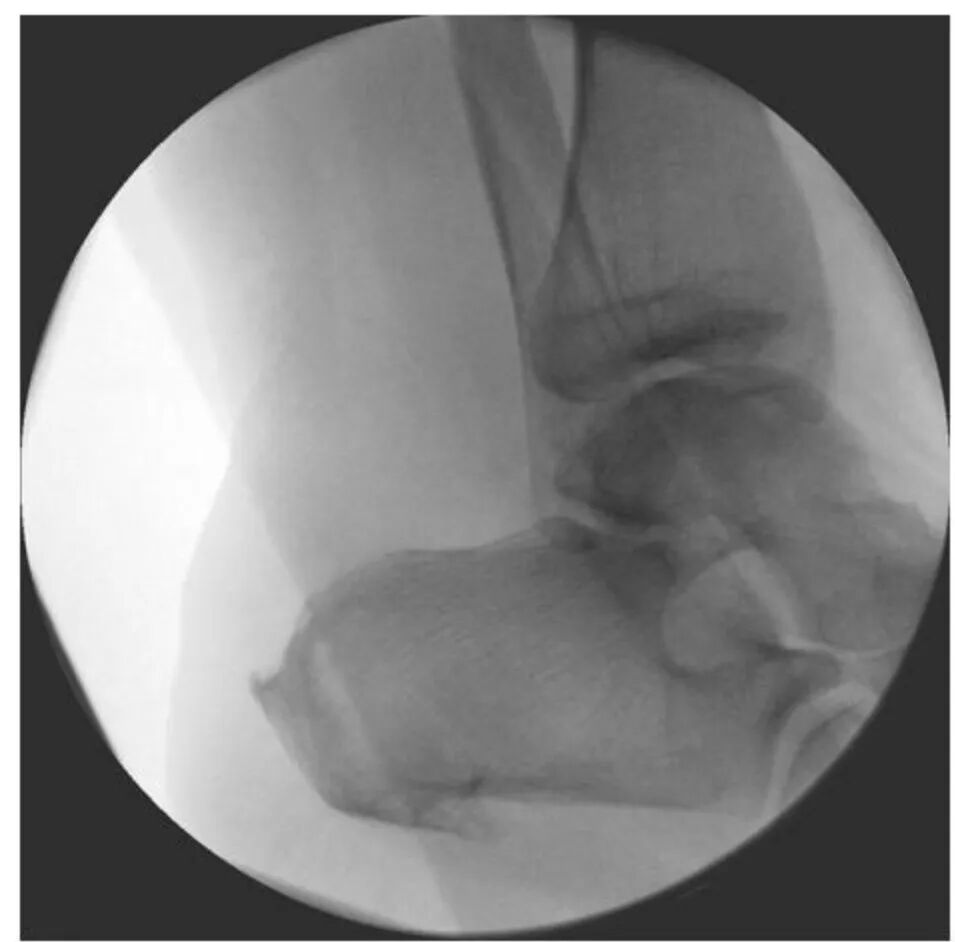

通过C臂机监视切除情况,应显示Haglund畸形被平滑切除。